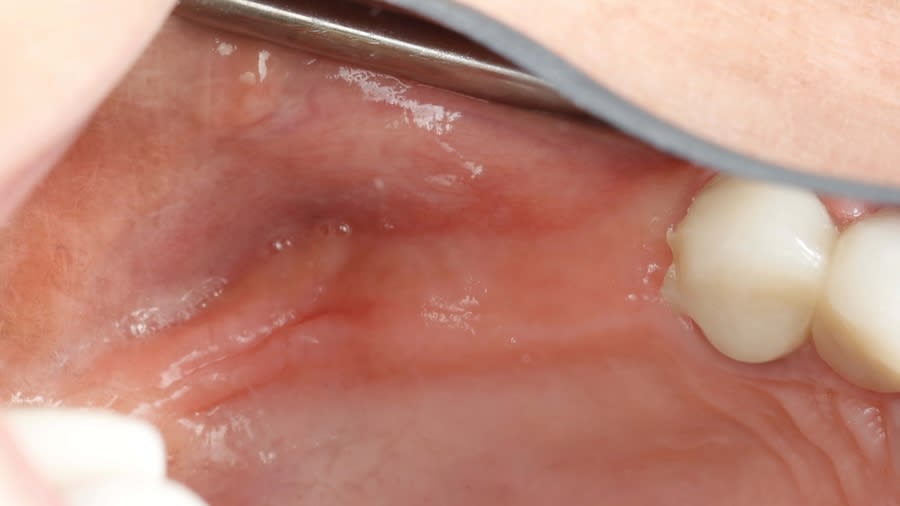

Case 1 (Figure 3 through Figure 24) depicts a 3-year follow-up of combined osseodensification sinus protocol IV in a severely resorbed maxillary ridge with ≤0.5 mm bone height in molar sites and horizontal deficiency at the first premolar site, using a two-stage approach for implant placement.

Step 1: Measure bone height at the osteotomy site on the CBCT. Measure ridge clinical width. A minimum of 7 mm alveolar ridge width is needed. Perform horizontal incision 2 mm to 3 mm palatally from the planned osteotomy site and elevate the flap using regular techniques of the clinician’s choice.